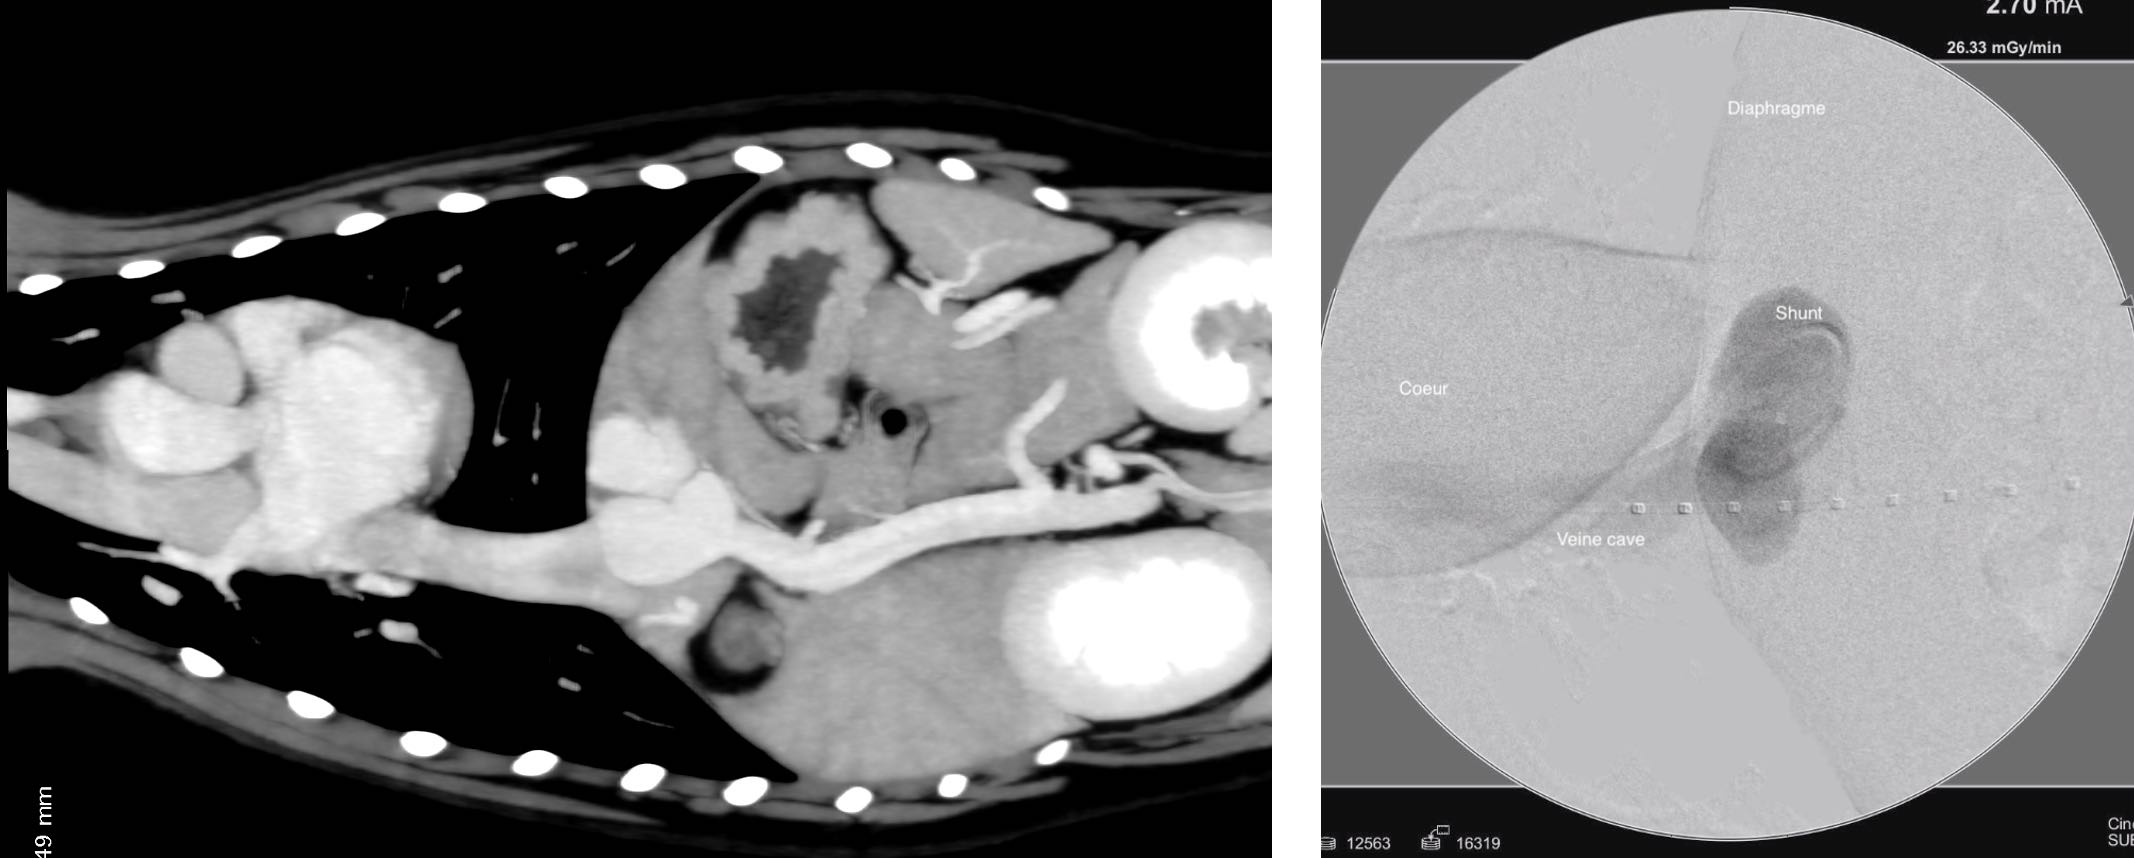

Une jeune chienne Border Collie de 8 mois présentée pour encéohalose hépatique a été diagnostiquée avec un shunt intra-hépatique de la division gauche du foie (persistance du ductus venosus), plus particulièrement le lobe latéral gauche. Le diagnostic a été établi après échographie et confirmation de l'anatomie précise du shunt par angioscanner triple phase.

Photo1 : Scanner hépatique, après injection de produit de contraste, coupe transverse. On observe un shunt intrahépatique de la division gauche du foie connectant directement la veine porte à la veine cave. On observe peu de vaisseaux porte intrahépatique.

Photo 3 (Droite) angiographie sélective du shunt peropératoire sous fluoroscopie (image en soustraction où le produit de contraste apparait noir), même orientation que la photo 2.